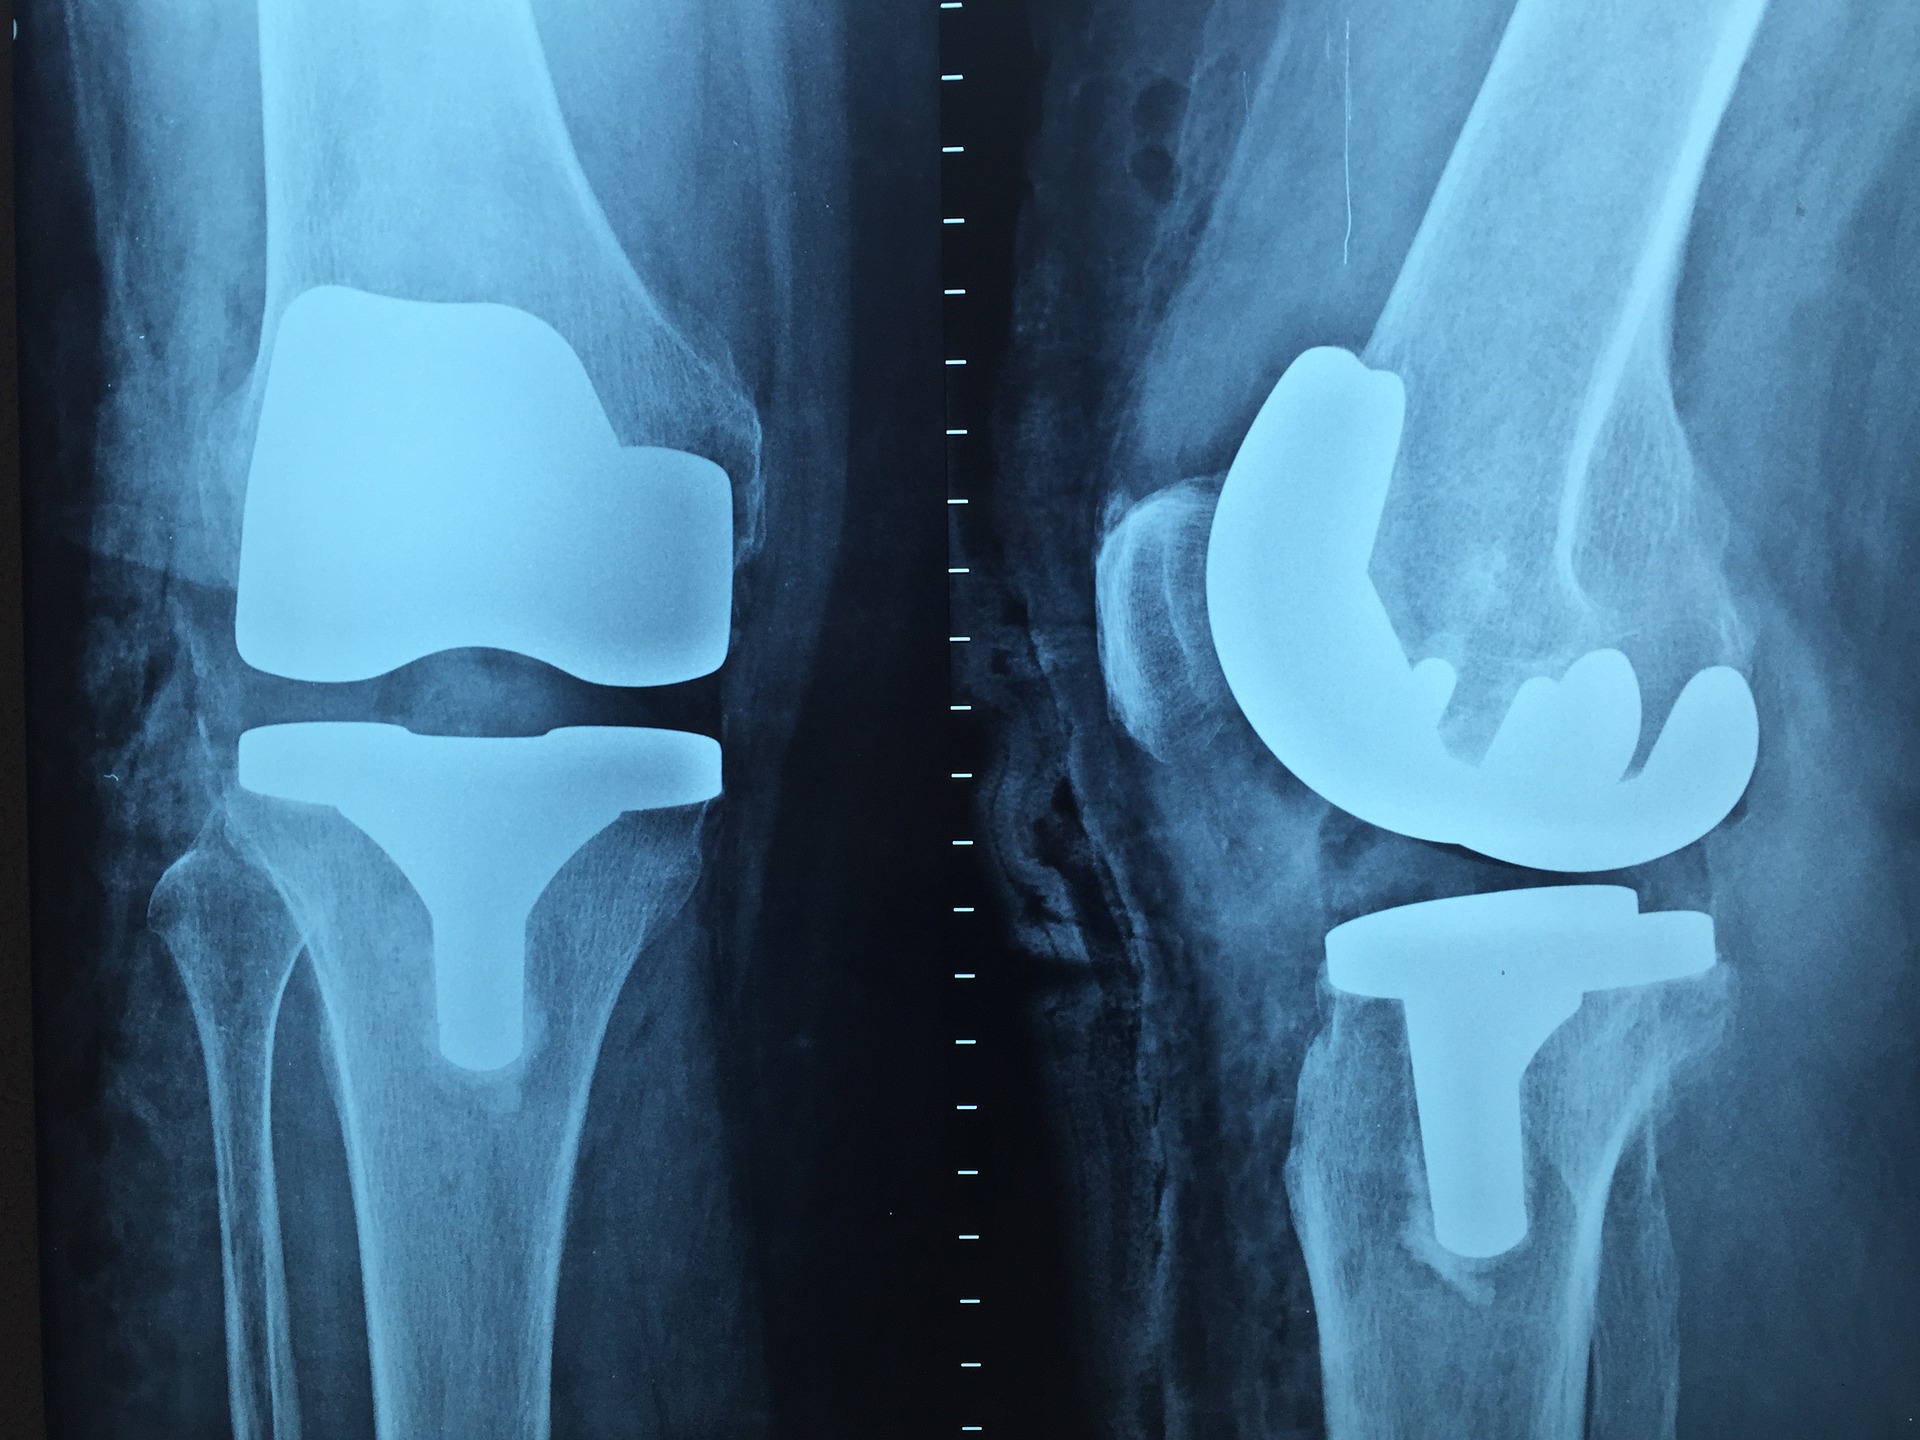

El servicio de ortopedia en consulta externa presta un servicio donde se realiza la valoración clínica, diagnostico, prevención y direccionamiento adecuado al tratamiento quirurgico y no quirurugico de alteraciones funcionales traumáticas y no traumáticas del aparato locomotor y sus estructuras asociadas.